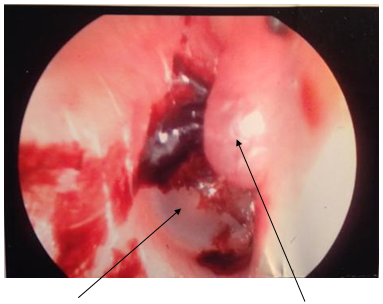

With the diagnosis of granuloma, the patient was scheduled for excision of the lesion under general anesthesia. This was performed two weeks following presentation. Photograph of the lesion is seen in Figure 1. It demonstrates a small blood clot on the superior aspect of the tympanic membrane. The inferior portion of the tympanic membrane is normal and there is a cystic-like lesion in the anterior superior canal wall. Interestingly, the inferior tympanic membrane is normal. At this time, it was felt that the lesion was primarily a granuloma arising from the ear canal.

Figure 1 Photograph of right external ear canal of patient demonstrating a herniation of the right TMJ capsule into the anterior canal wall (right arrow) through a patent foramen of Huschke. The lower half of the tympanic membrane is normal (left arrow). The superior portion of the tympanic membrane is covered with a blood clot.